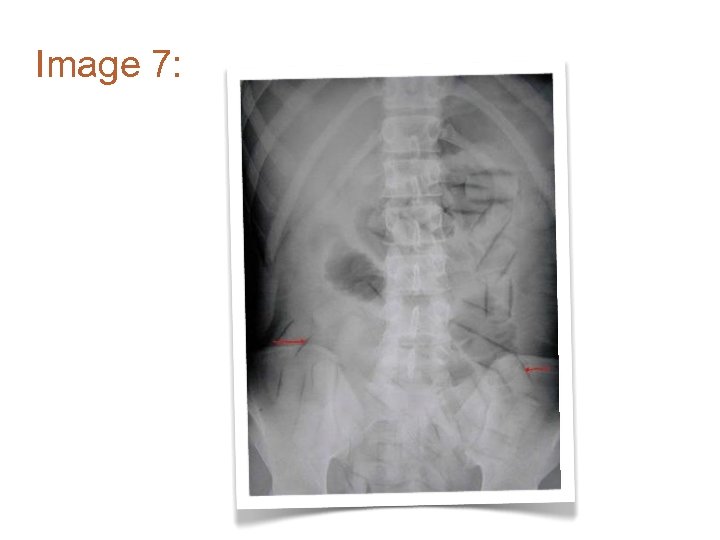

Image 7: